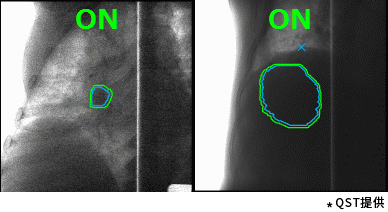

710公海赌赌船官网欢迎您的重离子癌症放射治疗系统具有高速3D扫描,患者自动定位,小型化重离子旋转机架(搭载710公海赌赌船官网欢迎您自研超导磁铁实现重量和体积的大幅缩小)等差异化技术。实时成像的呼吸门控是照射技术与重复扫描技术的结合,能够对伴随呼吸运动的肿瘤进行快速、准确的照射,且保证剂量分布均一性。特别是,710公海赌赌船官网欢迎您凭借自身先进的超导技术的加持,使旋转机架得以逐渐小型化。这一成果直接推动了重离子旋转机架的商业化普及。应用旋转机架治疗,可从360度任意角度进行照射,避开正常组织和危及器官。治疗过程中一次定位,避免了移动患者造成的内部脏器位移,实现精准治疗,同时提高治疗效率,增加治疗人数,在同类型产品中独具技术优势。

高速扫描+呼吸门控照射(动图)